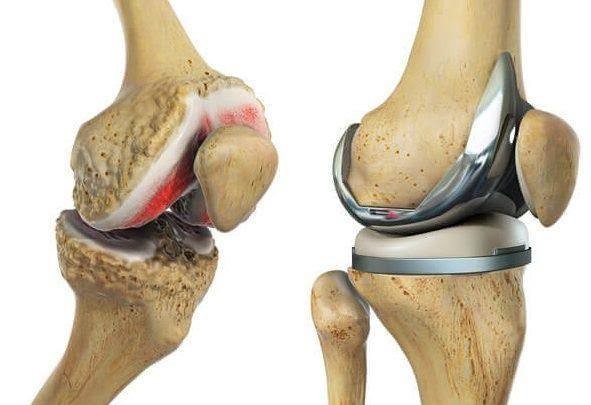

A total knee replacement (TKR) is a surgical procedure that resurfaces damaged knee joint surfaces with metal and plastic components to relieve severe pain and disability, most commonly caused by arthritis. It is typically recommended when other treatments fail to provide adequate relief.

- Resurfacing: The surgeon reshapes the ends of the femur and tibia and resurfaces the underside of the patella using durable metal and plastic implants.

- Components: The artificial knee typically includes a metal femoral component, a metal tibial plate, and a plastic spacer between them, often with a plastic “button” for the kneecap.

- Severe Pain: To relieve pain caused by osteoarthritis, rheumatoid arthritis, or post-traumatic arthritis.